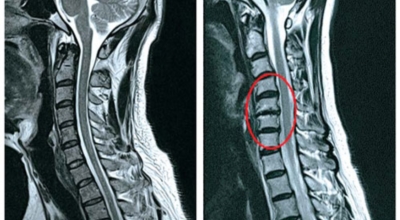

목디스크 증상이 나타날때 빨리 발견하여 비수술 치료를 받고 꾸준히 관리하는 것이 베스트이죠. 목디스크 환자 중 수술을 진행하는 환자는 2% 미만으로 현저히 적다고 해요. 수술을 진행하는 경우는 감각이 느껴지지 않는 마미증후군이나, 한쪽 다리가 눈에 띌 정도로 야윈 경우에만 진행하므로 올바른 자세 교정만으로도 충분히 호전될 수 있는 질병이죠. 목에 연관된 검사는 MRI나 CT를 이용해요. 그러나 전자의 경우 비용이 굉장히 비싸기 때문에 디스크 증세가 확실하다고 생각될 경우에만 선택적으로 하고 의무적으로 하는 건 아니니까 비용에 대해선 부담을 가지지 마시길 바래요.